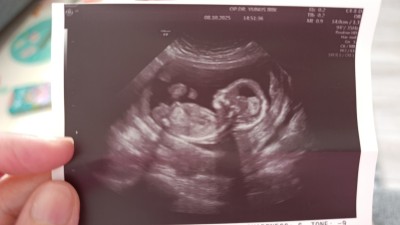

Kızlar çok rica ediyorum cinsiyet tahmini yapabilir mısınız henüz net bi şey denmedi

Nub çıkıntısına bakmaya çalıştım görüntülerden. Tam emin olamadım tabii ama kız olduğunu düşünüyorum. Gönlünüze göre olsun 😊

Sanki çıkıntısı var bana erkek gibi geldi Allah gönlünüze göre versin saglıklı sıhhatli doğmasını nasib etsin 🥰

12 haftalık misiniz banada erkek gibi geldi